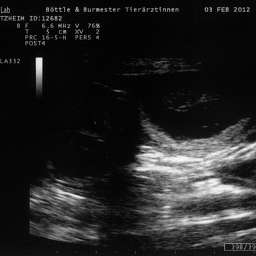

3.2.2012, 32.Tag: Der Ultraschalltermin ist vollbracht: Juhu, wir werden Eltern!!!

Aus Herzklopfen wurde Herzrasen und dann endlich, kurz vor der Herztablette, zeigte uns der Ultraschall 5 KLEINE WUNDER, gesunde Fruchthüllen, mit lebendigem Innenleben und pochendem Herzen. (...passte sehr gut zu unseren...)Wieviele es letztendlich werden, bleibt eine riesige Überraschung.

Bitteschön, ein kleines Filmchen mit dem Titel: "5 auf einen Streich, oder wie es in den Bauch hineinschallt, schallt es auch wieder hinaus."

4.2.2012, 33.Tag: Hier sind also die Fotos der kleinen Flauschmonster in ihren Höhlen.

Sucht Euch doch schon mal einen aus: